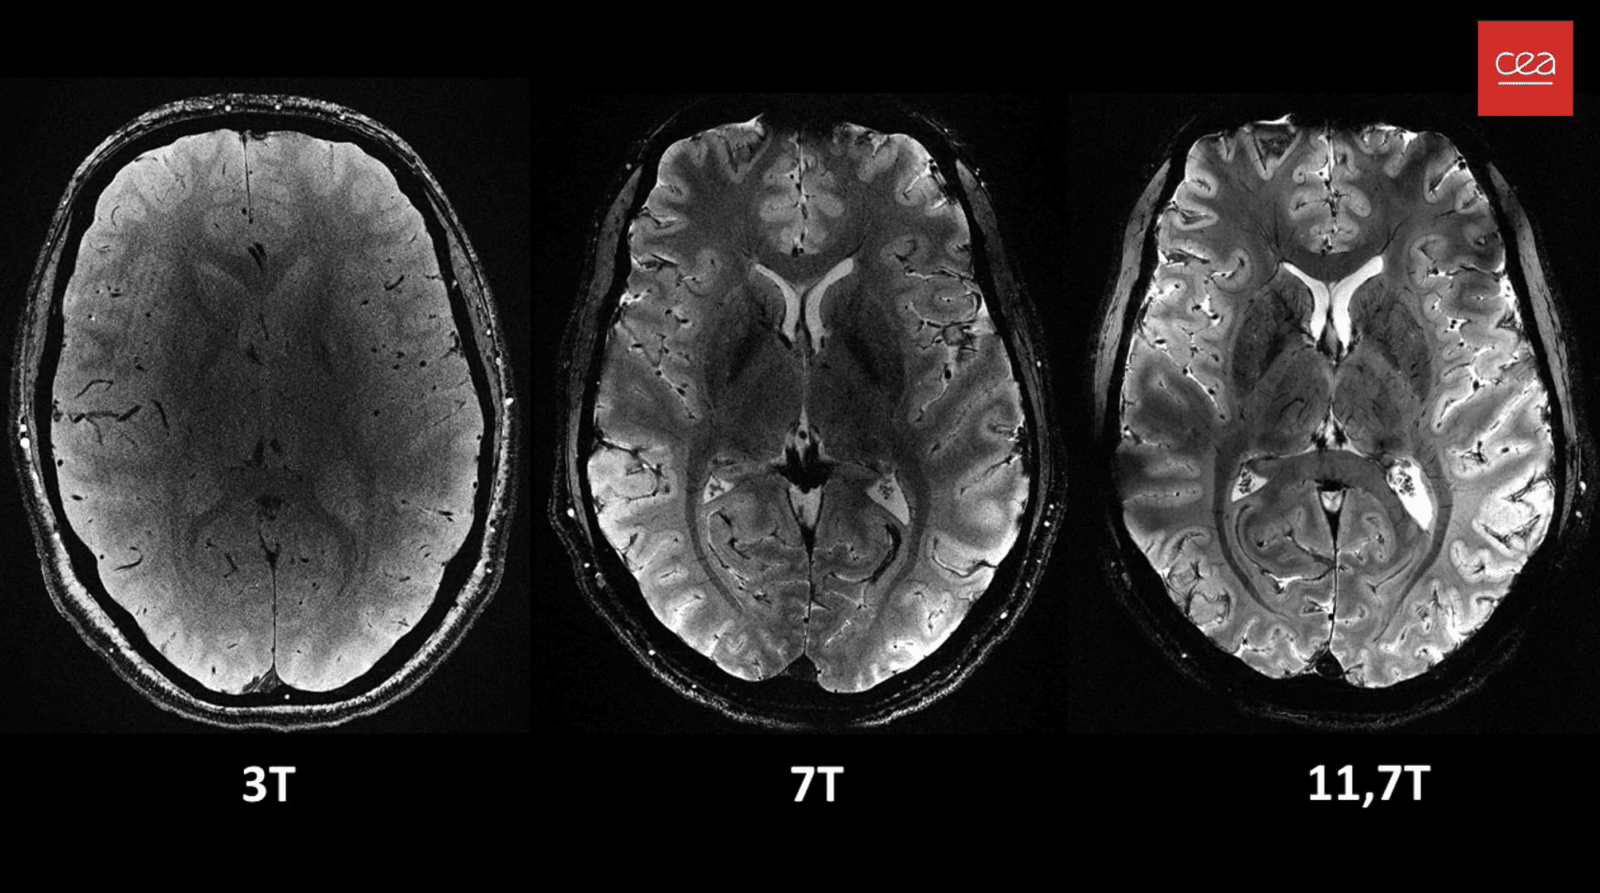

Opracowane przez Francuską Komisję Energii Jądrowej i Energii Alternatywnych (CEA) urządzenie Iseult MRI wytwarza pole magnetyczne o natężeniu 11,7 tesli (T). Dla porównania, konwencjonalne aparaty MRI powszechnie stosowane obecnie w szpitalach mają zwykle moc 1,5 lub co najwyżej 3 T.

Główną zaletą dodatkowej mocy jest to, że zdjęcia mózgu o znacznie wyższej rozdzielczości można wykonywać znacznie szybciej. W ciągu zaledwie czterech minut Iseult może rejestrować obrazy tkanki mózgowej o grubości do 0,2 mm w poziomie, a w “plasterkach” o grubości zaledwie 1 mm. Aby konwencjonalne aparaty MRI mogły wykonać zdjęcia o takiej rozdzielczości, pacjenci musieliby leżeć w całkowitym bezruchu przez ponad dwie godziny – najmniejszy ruch spowodowałby rozmycie zdjęcia, a to po prostu niewykonalne.